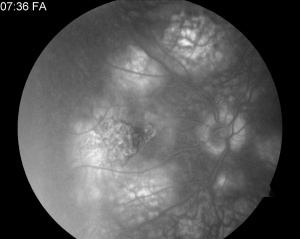

- Fluorescein angiography (FA): Active lesions exhibit early hypofluorescence (blockage) corresponding to the placoid lesions followed by late, irregular hyperfluorescent staining.[5] Early hypofluorescence may represent poor perfusion of the choriocapillaris or signal attenuation from overlying outer retina and/or RPE thickening. Late hyperfluorescence may be a result of vascular leakage, which resolves in subacute or healed lesions.[21]